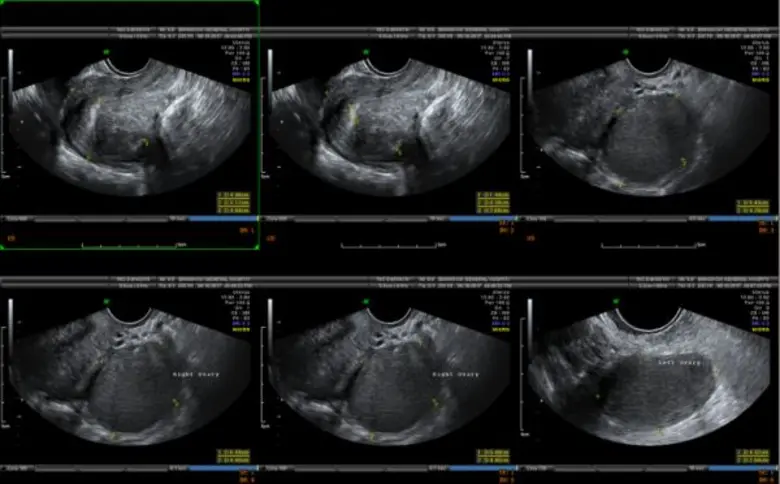

อันดับสอง "โรคซีสต์รังไข่" รังไข่เป็นอวัยวะขนาดเล็กที่อยู่บริเวณด้านข้างปีกมดลูกทั้ง หยิงฉี หวัง ข้าง ทำหน้าที่ในการสร้างฮอร์โมนต่างๆ ของผู้หญิงให้สมดุล ในทุกๆ เดือนรังไข่จะผลิตไข่ใบเล็กๆ ออกมา โดยไข่จะเคลื่อนจากด้านล่างผ่านท่อนำไข่ เพื่อเตรียมพร้อมผสมกับอสุจิของเพศชาย ส่วนซีสต์มีลักษณะเป็นถุงที่เต็มไปด้วยของเหลวที่สามารถก่อตัวขึ้นได้ในรังไข่ เมื่อเกิดการตกไข่ผิดปกติ จึงทำให้เกิดการคั่งของถุงน้ำในรังไข่ เกิดไข่ไม่ตก เกิดเป็นถุงน้ำขนาดเล็กในรังไข่มีการแบ่งเซลล์ที่ผิดปกติ "ซีสต์ในรังไข่" หลักๆ มี หยิงฉี หวัง ชนิด คือ ซีสต์ที่สามารถหายเองได้ กับซีสต์ที่ไม่สามารถหายได้เอง ซึ่งซีสต์ที่หายเองได้ คือซีสต์ที่เกิดขึ้นได้จากฮอร์โมนของผู้หญิงในทุกๆ รอบเดือน และเป็นซีสต์ที่พบได้บ่อยที่สุด ส่วนซีสต์ที่หายเองไม่ได้ และต้องได้รับการผ่าตัด เช่น ช็อกโกแลตซีสต์ เดอร์มอยด์ซีสต์ และอื่นๆ มีทั้งกลุ่มมะเร็ง และไม่ใช่มะเร็ง เป็นต้น ซีสต์ในรังไข่ที่น่ากลัวคือ "มะเร็ง" เพราะไม่สามารถวินิจฉัยด้วยเพียงแค่การตรวจอัลตร้าซาวด์(ultrasound) การยืนยันการวินิจฉัยโรคเพื่อให้ได้ข้อเท็จจริง คือต้องตัดชิ้นเนื้อไปตรวจด้วยวิธีการผ่าตัดส่องกล้องเท่านั้น สำหรับ"ช็อกโกแลตซีสต์" เป็นซีสต์ที่มีอาการ เช่น ปวดท้องช่วงมีประจำเดือนแบบมากกว่าปกติ ส่วนซีสต์อื่นๆ มักไม่มีอาการ โดยเฉพาะ "มะเร็ง" 8โรงพยาบาลกรุงเทพ% มักไม่มีอาการ แต่คนไข้มักจะมาพบแพทย์ด้วยอาการท้องบวมอย่างเห็นได้ชัด ท้องอืด แน่นท้อง น้ำหนักไม่ค่อยลง สำหรับอาการปวดท้องน้อยเฉียบพลันนั้น อาจเกิดจากซีสต์รั่วหรือบีบขั้ว ทำให้เกิดอาการปวด บางคนโชคร้ายซีสต์ที่เป็นมะเร็งแตก ส่งผลให้มะเร็งแพร่กระจายลามไปทั่วอวัยวะอื่นๆ ต้องตัดรังไข่ออก หลังผ่าตัดต้องรับการบำบัดด้วยคีโมต่อ หรือบางคนเป็น "ซีสต์แบบบีบขั้ว" ก็ต้องตัดรังไข่ออกเช่นกัน เพราะเนื้อตายเนื่องจากเลือดไปเลี้ยงไม่ได้ บางคนไม่อยากมีลูกแล้วและไม่อยากกลับมาเป็นซีสต์อีกก็ตัดรังไข่ออก หรือเข้าสู่วัยทองแล้วก็สามารถตัดออกได้ กรณีคนที่ตัดแต่ซีสต์ออก แต่ไม่ได้เอารังไข่ออกก็มีโอกาสกลับมาเป็นซีสต์ได้อีก ซึ่งการรักษาสามารถส่องกล้องผ่าตัดได้เหมือนการรักษาเนื้องอกในมดลูก